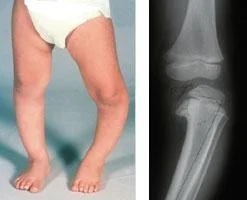

Pediatric Orthopedic